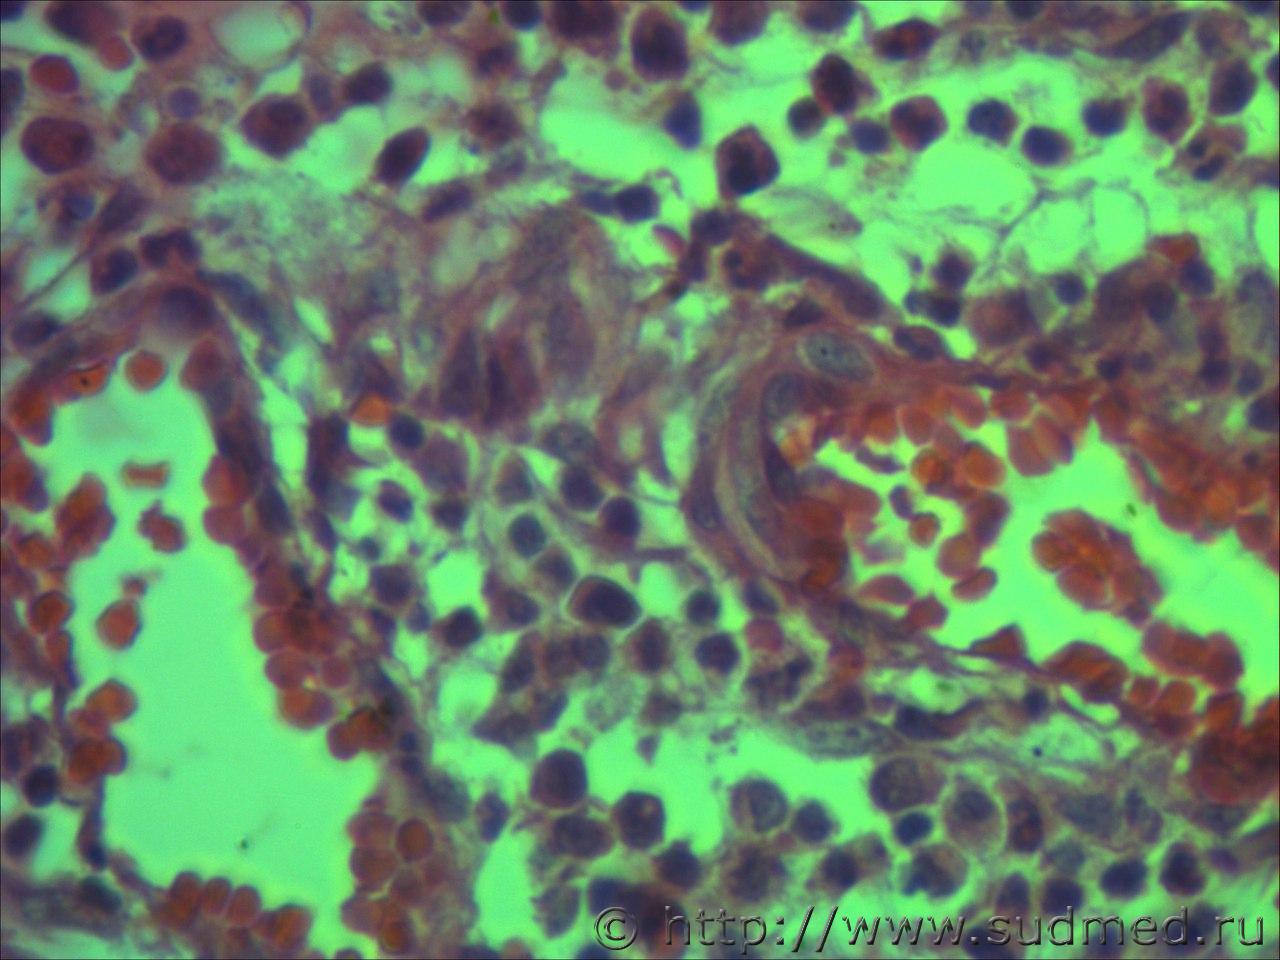

вижу что тяжи клеток эпидермиса проникающие в глубокие слои кожи и подлежащие ткани. Размеры клеток варьируют, слабовыраженное ороговение отдельных клеток, обильный воспалительный инфильтрат, пласты эпителиальных клеток в виде гнезд отделяются от эпидермиса. Склонен к ПКР

круглоклеточная опухоль, эпителий без патология

Фото низкого качества.

Попробую предположить,что на фото плазмоцитома и псевдокарциноматозная гиперплазия.